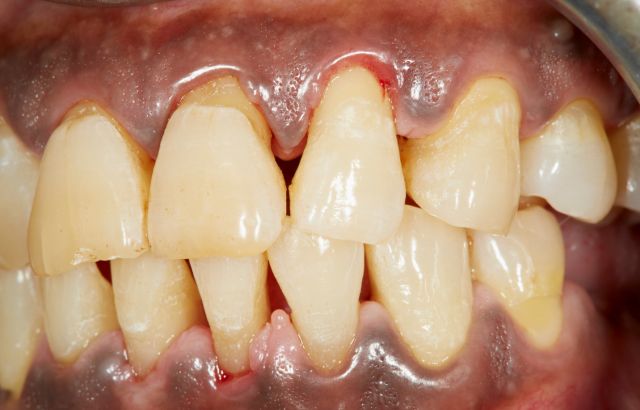

Parodontitis is een ernstige aandoening in de mond, maar ontstaat niet van de ene op de andere dag. Het begint met een ontsteking aan het tandvlees: gingivitis. Wanneer dit niet wordt behandeld, zal de ontsteking zich uitbreiden naar het kaakbot. Dan spreek je van parodontitis. Bacteriën in tandplaque en tandsteen -wat ook vaak de veroorzakers van gingivitis zijn- kunnen verder uitbreiden in de pockets. Dit is de ruimte tussen je tand en het tandvlees. De ontsteking tast de vezels in de pocket aan, waardoor deze ontsteking nóg dieper wordt en er nog meer tandplaque in de pocket kan komen. Het kaakbot wordt afgebroken. Het “parodontium” (de tandheelkundige benaming voor het “ophangsysteem” in je mond) is beschadigd en zal zijn werk niet meer kunnen doen. Gevolg? De tand heeft geen houvast meer en zal uitvallen.

• Rood en/of gezwollen tandvlees

• Bloedend tandvlees

• Teruggetrokken tandvlees